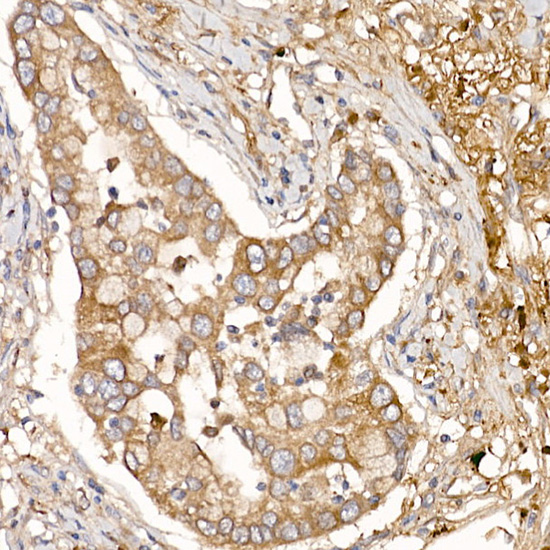

Immunohistochemistry of paraffin-embedded human lung cancer using NUMB Rabbit pAb.